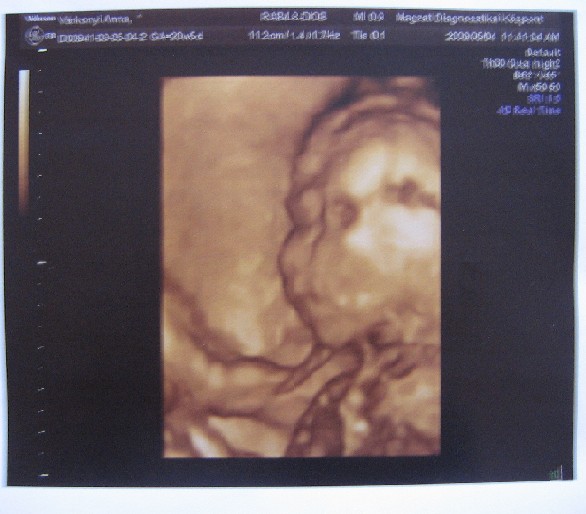

TÉnyleg a következő képek lesznek az igazán "jók", de ez is édes, és gondolom tök mindegy mennyire szellemképes, mégis nézegetitek "állandóan"

Nagyon rendes a doki, mert azon a kb. 30 heti UH-n hosszú percekig próbálkozott, hogy minél jobb képet tudjon varázsolni. És ha most összehasonlítom Ádámmal, teljesen olyan, mint ott látható volt.